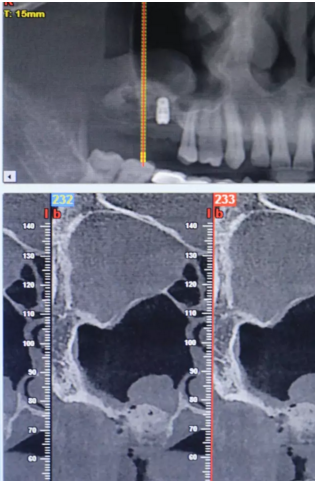

【病例分享】上頜竇大囊腫外提升